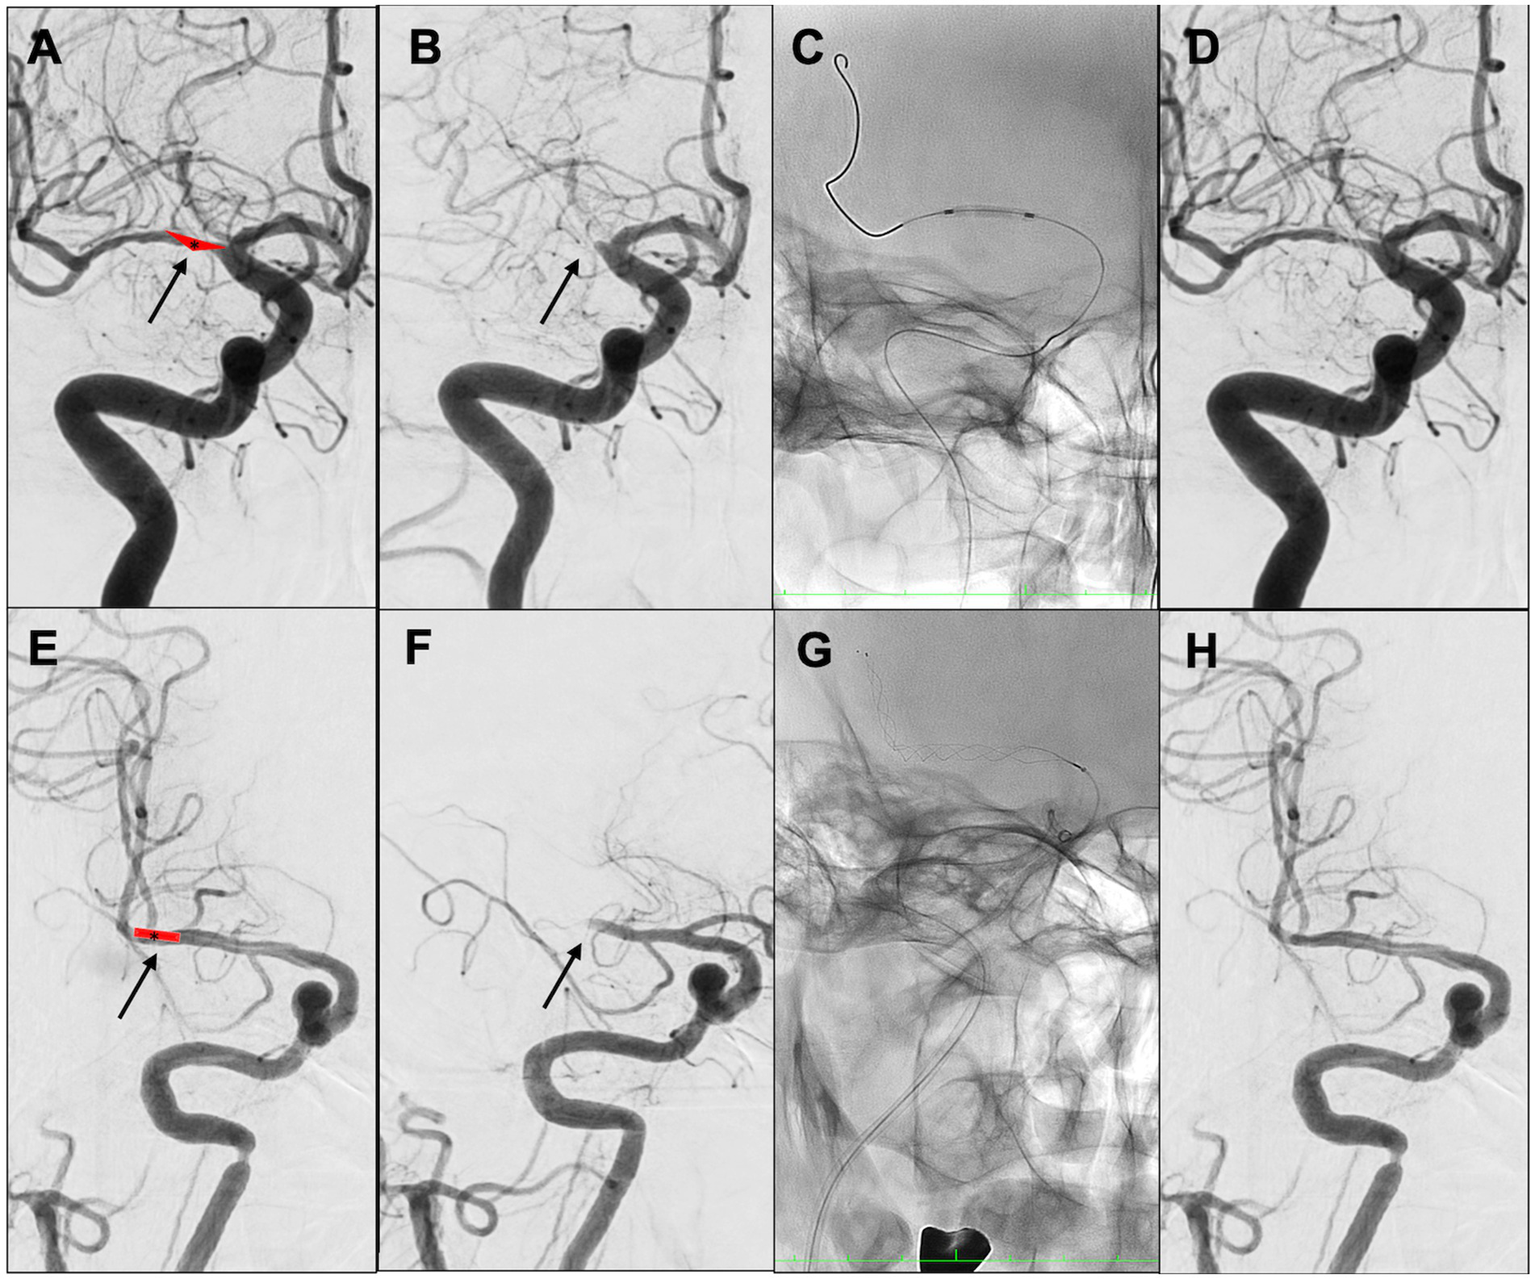

A multicenter observational study from Korea determined that occlusions of a truncal type were correlated with a lack of responsiveness to stent retrievers and were the fundamental cause of strokes (36). The subjects were patients undergoing MT for intracranial occlusions of the internal carotid artery, MCA, proximal MCA, intracranial vertebral artery, or basilar cerebral artery. The occlusions were classified as either branching-site occlusion or truncal-type occlusion. Branching-site occlusion was defined as at least one of the following three conditions (Figure 5); (1) anterior communicating artery collateral flow that could not proceed to the contralateral ICA or MCA because it involved the internal cerebral artery bifurcation site (T occlusion); (2) direct visualization of a Y-or T-shaped filling defect involving a bifurcation site (Y-or T-shaped clot); and (3) another branch could not be visualized or was only partially visualized when the retriever was deployed to a branch across the occlusion site. Truncal-type occlusion, on the other hand, was defined as all branches and bifurcations visible beyond the occluded vessel, including those observed at recanalization. After a comprehensive evaluation involving chest electrocardiogram, echocardiography, cardiac CT, and cervical vascular echocardiography, the patients were classified as having embolic or non-embolic LVO. Of the 259 patients (mean age 70.3 years; male/female ratio 132:127), 83.4% had embolic LVO. Multivariate analysis revealed that younger age, prior coronary artery disease, and truncal-type occlusion were independently linked to the absence of embolic LVO (OR, 9.07; 95% CI, 3.74–22.0). Furthermore, truncal-type occlusion was associated with a higher frequency of reocclusion and a longer time to recanalization during stent retriever treatment. In a subanalysis of this study, truncal-type occlusion was associated with 93% of ICAS-related LVO and 10% of embolic LVO (p < 0.01) (35), whereas branching-site occlusion was associated with 7% of ICAS-related LVO and 90% of embolic LVO. In a separate study among 115 LVO patients in China, truncal-type occlusion was present in 93% of ICAS-related LVO and 10% of embolic LVO, while branching-site occlusion was observed in 7% of ICAS-related LVO and 90% of embolic LVO, yielding a significant difference between the two LVO types (p < 0.01 for each). The area under the curve of ICAS-related LVO in truncal-type occlusion was 0.916, with the sensitivity of 92.86% and specificity of 90.41% (36). CT angiography can also assess truncal-type occlusion, and although it is not a direct predictor of pathogenesis, branching-site occlusion as determined by CT angiography has been reported to independently predict the success of recanalization with stent retrievers (OR, 8.20; 95% CI, 3.45–19.5) (37). Representative cases of truncal-type occlusion/branching-site occlusion are shown in Figure 6.

Figure 6

Representative cases of truncal-type occlusion/branching-site occlusion. (A–D) Truncal-type occlusion. (E–H) Branching-site occlusion. (A) Schema of in situ thrombus of right middle cerebral artery (MCA) M1 truncal type (asterisk). (B) Initial angiography shows occlusion of right MCA M1 (arrow). (C) Angioplasty. (D) Identification of residual stenosis in the right MCA M1 (ICAS-related LVO). (E) Embolic schema of the right MCA M1/M2 bifurcation (asterisk). (F) Initial angiography showed occlusion of right MCA M1 (arrow). (G) Stent retriever was deployed. (H) After retrieval of red thrombus, the bifurcation was found to be occluded. Angioplasty and stent retrieval were then performed.